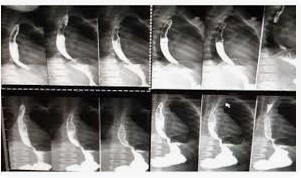

Acalasia

Acalasia - típico aspecto de "bico de pássaro"

Espasmo difuso

Espasmo difuso - padrão "corkscrew"